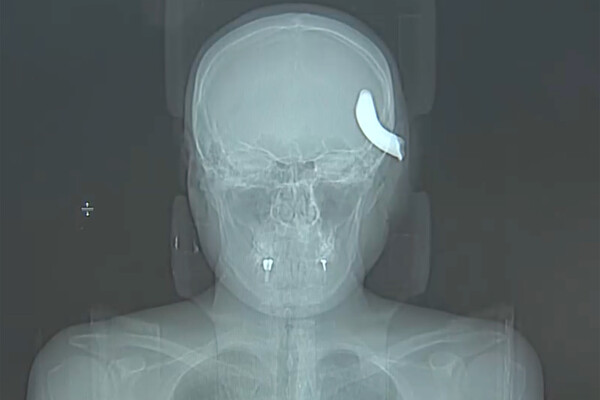

В Санкт-Петербурге врачи Елизаветинской городской больницы спасли 34-летнего мужчину, которому в голову вошел металлический крюк. Об этом врачи больницы рассказали в беседе с журналистами телеканала «Санкт-Петербург».

Инцидент, в результате которого пострадал мужчина, произошел в апреле. Петербуржец помогал другу с машиной, которую тянули на тросе, когда часть сломавшегося крюка отлетела ему в голову. В медицинское учреждение пострадавшего доставили в тяжелом состоянии.

На извлечение фрагмента крюка врачи потратили три часа. В процессе операции пациенту удалили часть костной ткани.

По словам нейрохирурга больницы Айгази Кискаева, мужчина сразу после операции показал положительную динамику: у него восстанавливается речь и функции правой руки, которые были нарушены из-за несчастного случая.